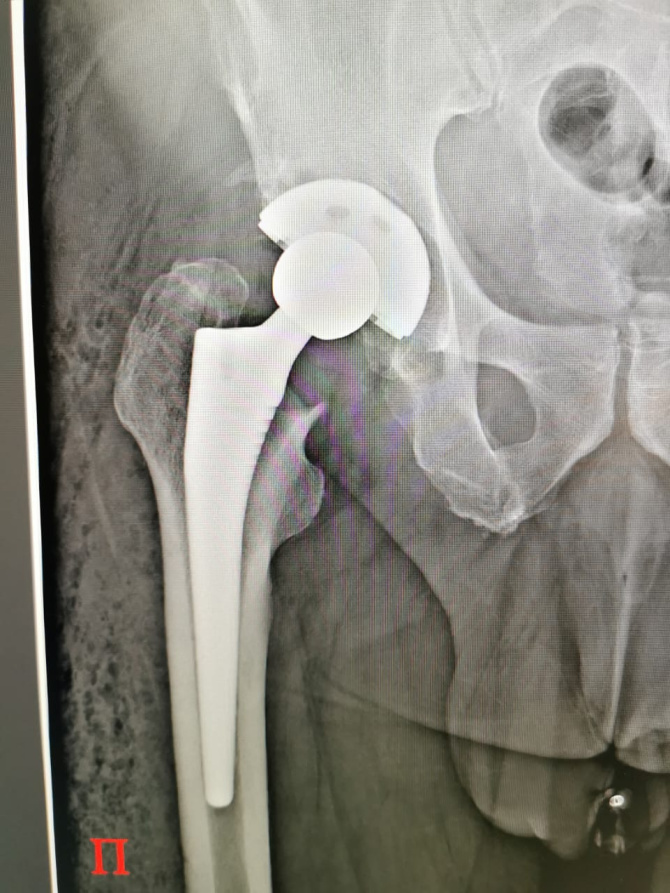

- Протезирование коленного и тазобедренного суставов. Они выполняются по квоте: коленные - по федеральной, тазобедренные - по региональной. Также востребованы артроскопические операции на плечевом суставе по федеральной квоте, восстановление связок на коленном суставе; операции на стопах - по федеральной и региональной квотам. С начала года мы провели 126 операций по протезированию тазобедренного сустава, 94 - коленного, 222 артроскопических операции

Пациент несколько дней проводит в хирургическом отделении, затем 10 дней в отделении реабилитации. Полтора месяца ходит на костылях, еще полтора с тросточкой - и все. За 4-5 месяцев подвижность, как правило, восстанавливается полностью. Через 7-8 месяцев уже можно ставить второй сустав - при необходимости.

-Конечно. И самый хороший результат показывает операция на тазобедренном суставе.